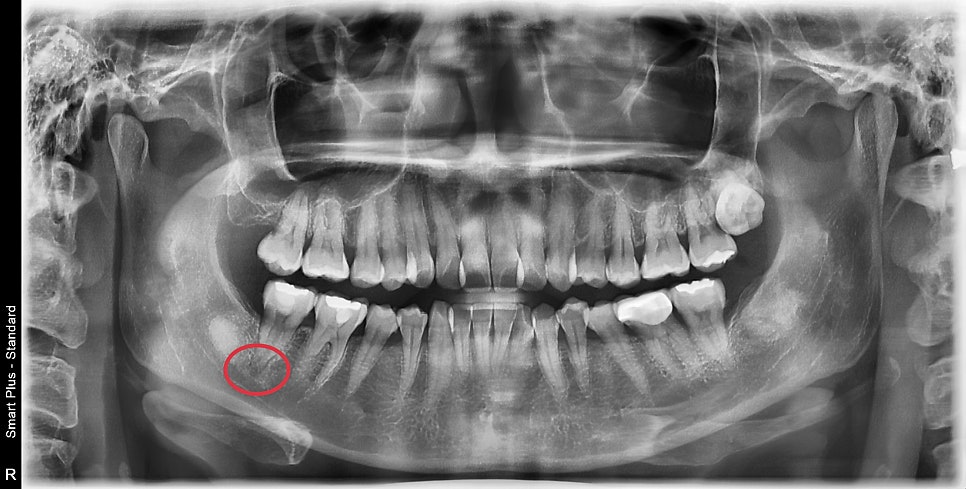

오른쪽 아래 맨 끝 쪽 어금니가 불편감이 있어서 내원해 주셨습니다.

엑스레이상에서 이미 뿌리 쪽에 염증소견을 보이며

구강 내 사진에서도 과거에 치료했던 금으로 된 인레이 주변으로

크랙 라인이 관찰되고 있습니다.

해당 치아는 과거의 넓은 범위의 수복물이 있지만 상태는 불량해 보였고

엑스레이에서 뿌리 쪽에 염증소견이 보였습니다.